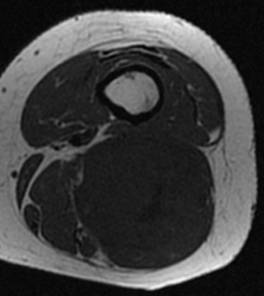

Synovialosarcome. Noter l’aspect hétérogène en T1, T2 et après injection de gadolinium

Synovialosarcome